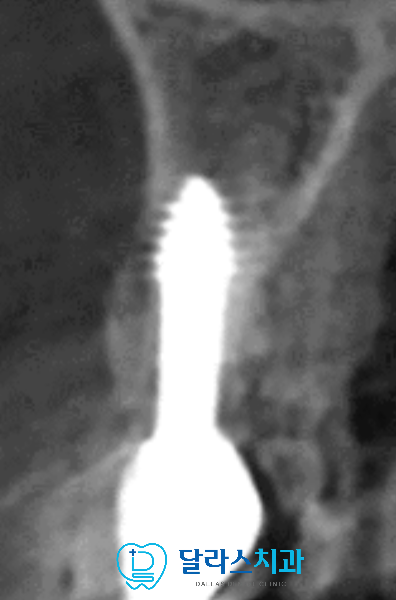

입체적인 CT를 촬영하여 최종확인해보면

기저골에 식립 4세대 임플란트는 큰 부작용 없이

주변 부분이 골로 둘러싸여서 안정적으로 자리한 것이 확인됩니다.